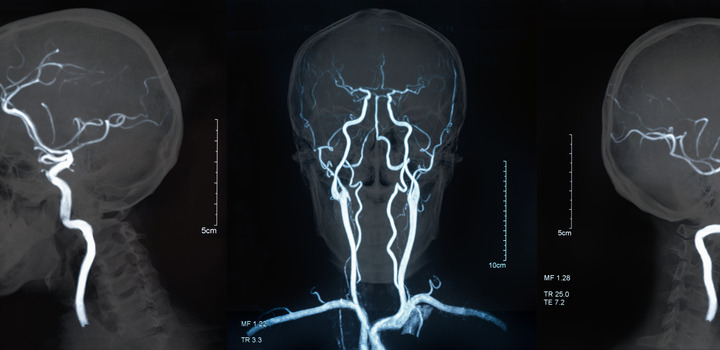

L’ictus dal latino “colpo” – stroke in inglese – è un evento cerebrovascolare che capita d’improvviso, anche in pieno benessere, in modo inatteso. Si verifica, nell’80% dei casi, quando un’arteria cerebrale si chiude improvvisamente, determinando un’ischemia, cioè la brusca interruzione dell’apporto di sangue a una regione dell’encefalo. Solo nel 20% dei casi si verifica invece un’emorragia cerebrale per rottura di arteria.

L’OMS (Organizzazione Mondiale della Sanità) definisce l’ictus come una perdita di funzione cerebrale a insorgenza rapida, i cui sintomi durano almeno 24 ore e sono attribuibili esclusivamente a cause di natura vascolare. I fattori di rischio principali dell’ictus o una cardiopatia sono: l’ipertensione, l’aterosclerosi, il fumo di sigaretta e l’abuso di alcol, la sedentarietà, questi favoriscono altri fattori di rischio quali il sovrappeso e il diabete mellito. Anche se l’ictus è la terza, non la prima, causa più comune “Disability-Adjusted Life Years” (DALY), ovvero, gli anni di vita potenziali persi a causa di una morte prematura, includendo gli anni di vita “sana” persi, in virtù del cattivo stato di salute o di disabilità, nei paesi più sviluppati. È anche uno dei più costosi da trattare. Parte della spesa è dovuta a problemi secondari nel periodo post-ictus, tra cui: cognizione, memoria, capacità di attenzione, dolore, perdita di sensazioni, problemi psicologici e problemi di mobilità ed equilibrio. Le possibili conseguenze di un ictus cerebrale sono: paralisi di un braccio o di una gamba, di un’intera metà del corpo (emiparesi) o di metà del viso (paresi facciale). Difficoltà di deambulazione: a causa di paralisi, di aumentata tensione muscolare (spasticità) o anche di disturbi della sensibilità la capacità di camminare è ridotta.